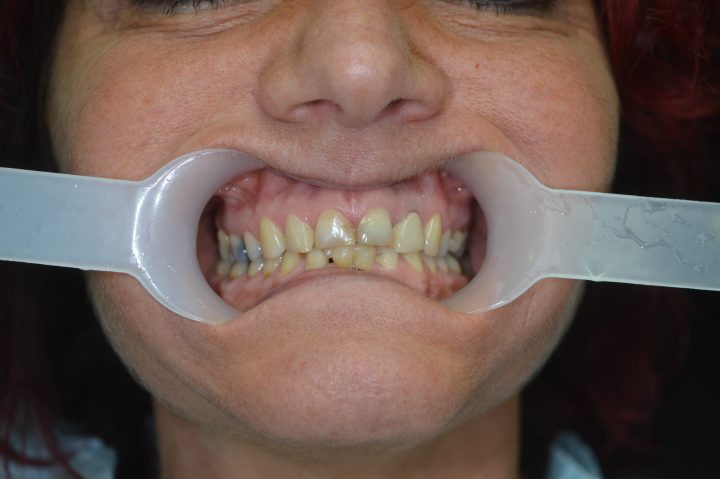

Ibrahim

Ibrahim ist einen von den französischen Patienten, wer früher sowohl oben, als auch unten herausnehmbare Zahnersatz hatte. Die Prothese hatte große Gaumenplatte, und deswegen konnte er die obere nicht tragen.

Er hatte ständig Brechreiz, und hat immer gewürgt, daneben war die Stabilität auch problematisch.

Die Prothesen haben sich ohne Klebstoff bewegt, und er hat sich aufgeregt, wenn er gesprochen hat. Er hatte davon Angst, dass die Prothese einmal ausfällt. Deswegen hat er die Klinik besucht.

Er hat oben und unten festsitzende Prothese auf Implantaten bekommen, womit er restlos zufrieden war. Diese Prothesen bewegen sich nicht weder beim Kauen, noch beim Sprechen.

Dank der Prothese, die keine Gaumenplatte hat, kann er sorglos den Zahnersatz tragen.